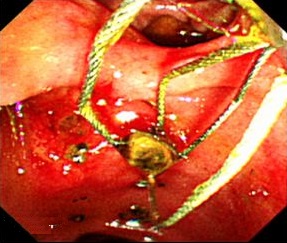

砕石術画像

総胆管結石症と診断された場合には、まずERCP(逆行性胆道造影)を行い、所見に応じて砕石・排石を行います。結石の大きさに応じて、内視鏡的に乳頭部のバルーン拡張ないし(EST)切開術を施行します。大きい総胆管結石でもほとんどの場合は内視鏡的に砕石することが可能ですが、内視鏡的治療が困難な場合は手術を行います。